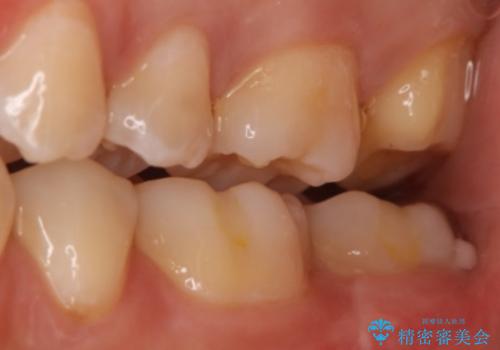

奥歯を治療したい フルジルコニアクラウン

- 99000円(フルジルコニアクラウン+仮歯)費用は治療当時の料金となります

虫歯の範囲が広い場合、大きく削る必要があるので部分的に詰めるインレーではなく、クラウンでの治療になることがあります。